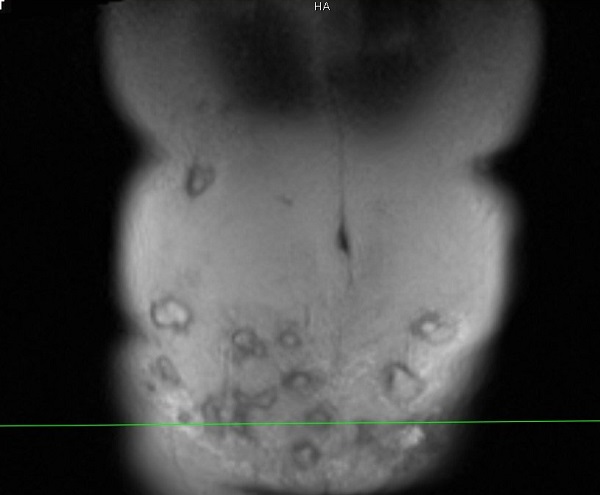

Hơn 20 khối áp xe hình thành trong bụng bệnh nhân, ảnh BSCC.

Bác sĩ Minh cho biết vùng thành bụng của bệnh nhân bị viêm nhiễm nặng, vùng da ngoài thành bụng có màu đỏ, sờ bên trong có hàng chục khối u cục, áp xe.

"Bệnh nhân có tới hơn 20 khối áp xe trong ổ bụng và vùng tiêm rộng nên việc lấy hết ổ áp xe này là không dễ dàng. Với những khối áp xe ở vị trí cao như hạ sườn thì quá trình xử lý sẽ để lại sẹo, gây mất thẩm mỹ", bác sĩ Minh nói.